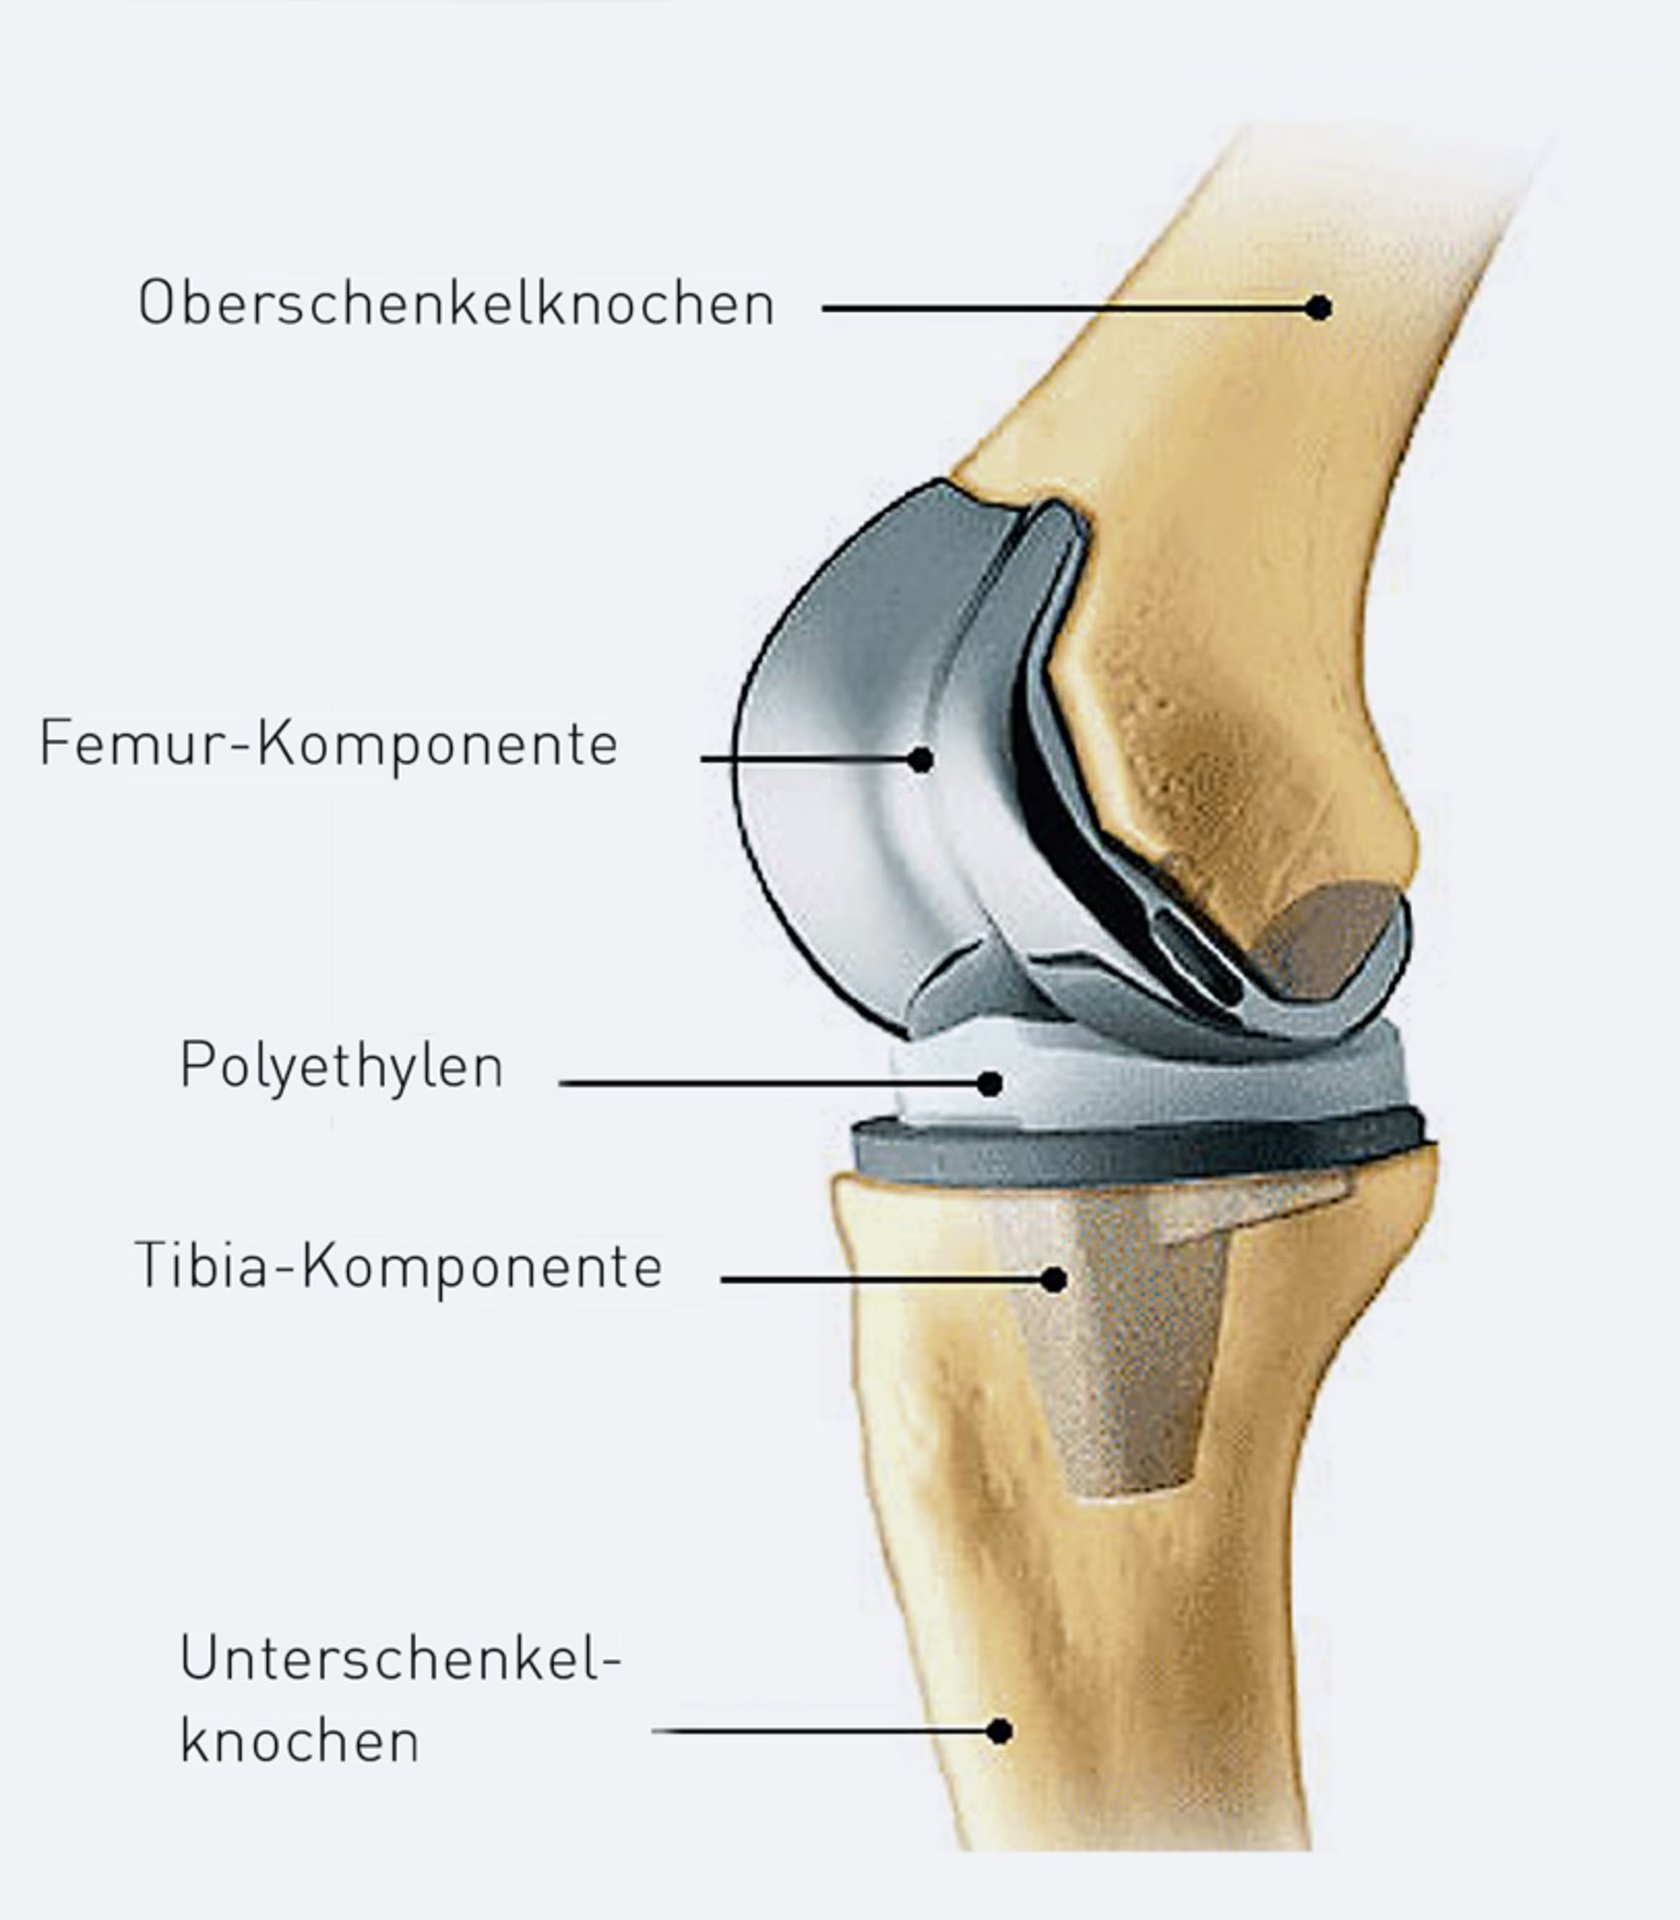

- Fjernelse af beskadigede dele: Knæskallen forskydes forsigtigt til siden. Kirurgen fjerner derefter det ødelagte brusk fra enderne af lårbenet (femur) og skinnebenet (tibia), samt menisker og i de fleste tilfælde det forreste korsbånd.

- Tilpasning af knoglerne: Ved hjælp af præcise skæreguider saves knogleenderne til, så de passer perfekt til protesekomponenterne.

- Permanent Protese: Når alt er perfekt, fjernes prøveprotesen, og de endelige protesedele fastgøres. Dette kan gøres med knoglecement (cementeret) eller ved at protesen har en ru overflade, som knoglen kan vokse ind i (ucementeret). I nogle tilfælde erstattes også bagsiden af knæskallen.